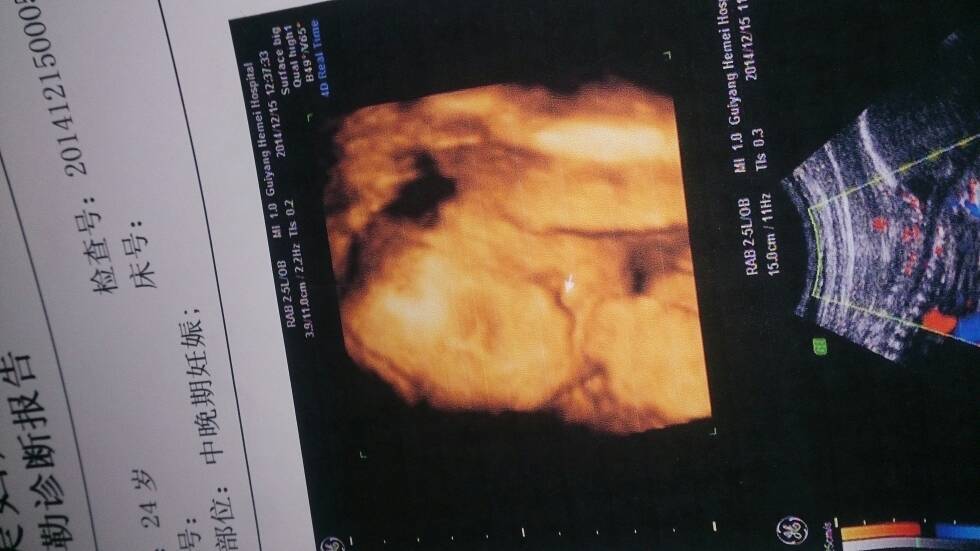

宝宝有唇裂我不想放弃 想生下来 但是不知道男宝女宝 大家帮忙看看 给点意见谢谢

我的彩超单子上是看不出来的,鼻子有,看起来跟正常宝宝一样